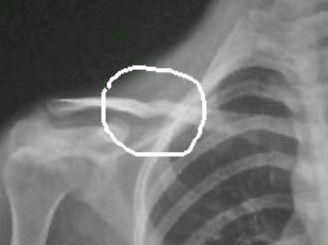

锁骨炎的症状图片

锁骨炎的症状图片,舌头炎的症状图片

小知识:锁骨骨折的症状是什么?